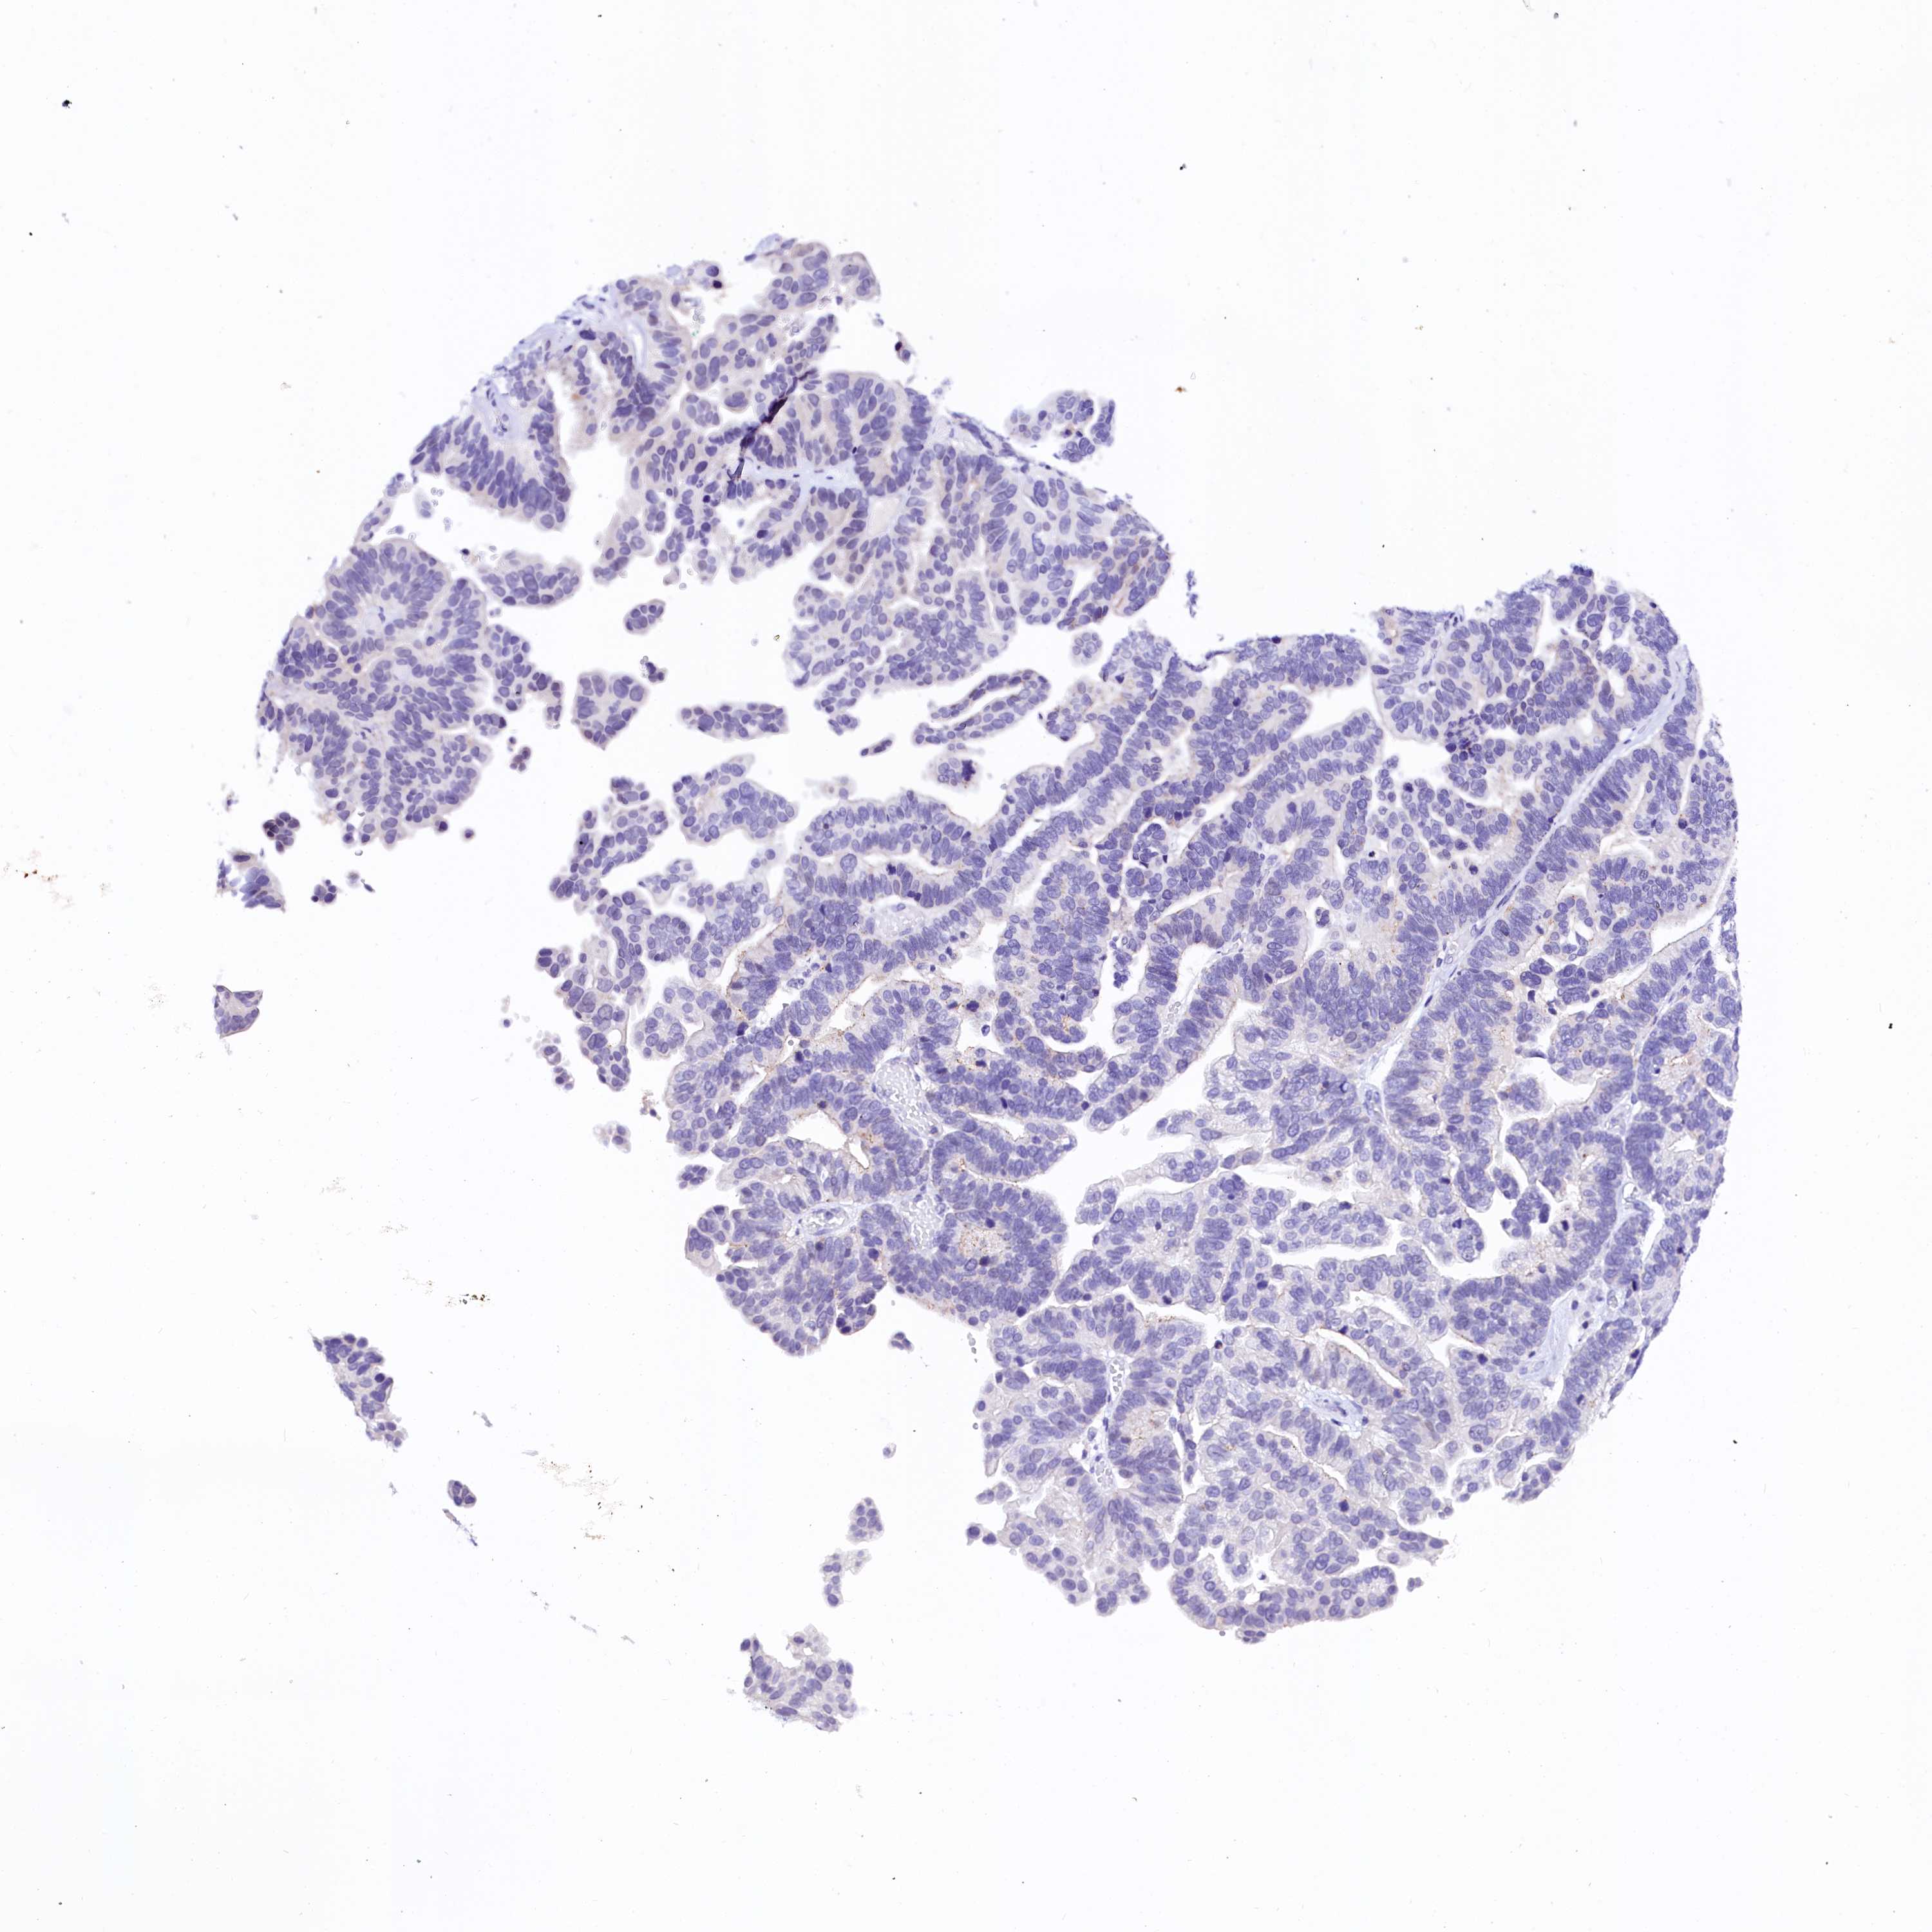

OVARIAN CANCER - Protein expressioni

A mouse-over function shows sample information and annotation data. Click on an image to view it in a full screen mode. Samples can be filtered based on level of antibody staining by selecting one or several of the following categories: high, medium, low and not detected. The assay and annotation is described here.

Note that samples used for immunohistochemistry by the Human Protein Atlas do not correspond to samples in the TCGA dataset.

Antibody stainingi

Antibody staining in the annotated cell types in the current human tissue is reported as not detected, low, medium, or high, based on conventional immunohistochemistry profiling in selected tissues. This score is based on the combination of the staining intensity and fraction of stained cells.

Each image is clickable and will lead to virtual microscopy that enables deeper exploration of all samples and also displays staining intensity scores, fraction scores and subcellular localization as well as patient and tissue information for each sample.

Antibody HPA039453

Cystadenocarcinoma, serous, NOS

Carcinoma, endometroid

Cystadenocarcinoma, mucinous, NOS

Carcinoma, NOS